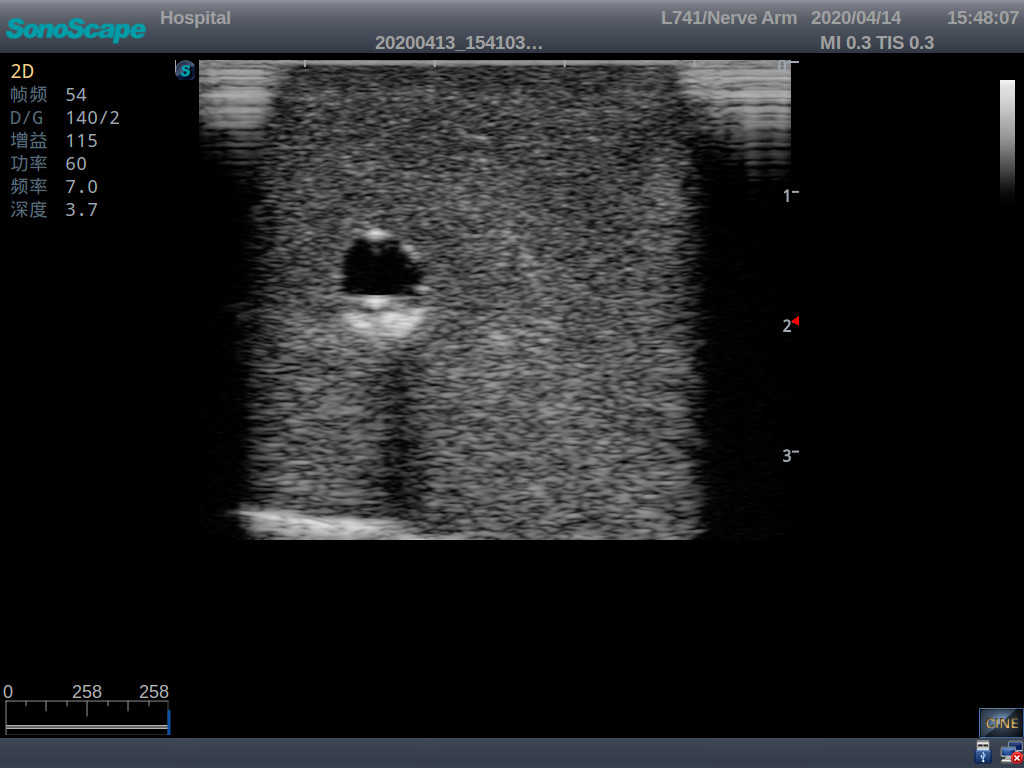

2) It can be used by real ultrasound machines

3) Clear and real images of the tissues and organs (basilic vein and superior vena cava)

6) Detect whether the catheter is properly placed